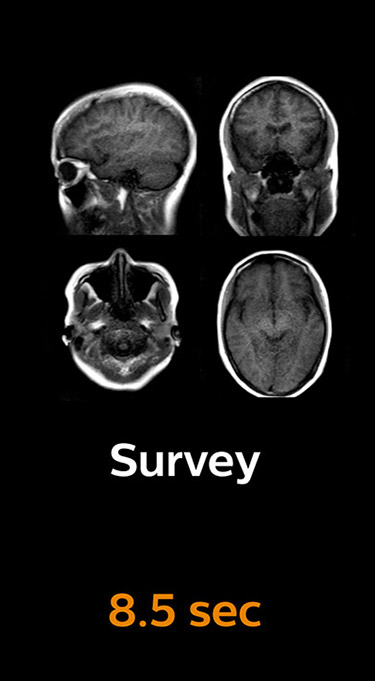

Scanning time reduction in brain MRI with Compressed SENSE

With Compressed SENSE, the scan time for the routine brain examination at KNC was reduced from 15:48 to 10:19 minutes, which corresponds to 35% reduction.

Brain with Compressed SENSE

Ingenia 3.0T CX

Scan time 10:19 min.